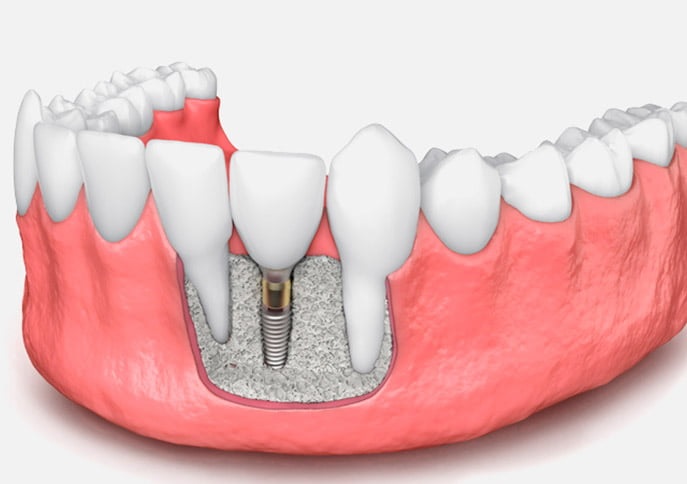

Los huesos se utilizaban para producir injertos óseos alogénicos, los cuales se fabrican normalmente con huesos de otras personas extraídos en cirugías, pero bajo del consentimiento de los donantes.

Los odontólogos utilizan los injertos alogénicos en los pacientes que cuentan con la suficiente densidad ósea para los injertos.